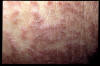

Eczema asteatósico severo

Eczema asteatósico severo.